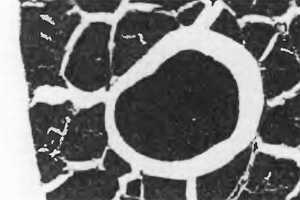

В 1976 г. Simons и Stolov [253] использовали критерии миофасциальных триггерных точек при изучении мышц собак на наличие болезненного пятна, определяемого в пальпируемом уплотненном пучке по сравнению с таковым, определяемым у человека. Под общим обезболиванием у животных одинаковая локализация в мышце была выявлена как путем пальпации, так и при расширенной биопсии. На поперечных срезах мышц были видны изолированные крупные округлые мышечные волокна и группы темноокрашенных, увеличенных в размерах округлых мышечных волокон (рис. 2.23).

Рис. 2.23. В центре рисунка показано гигантское округлое мышечное волокно, окруженное пустым пространством, которое вполне могло возникнуть в результате значительного локального энергетического кризиса. В этом пространстве могут находиться субстанции, способные повысить чувствительность прилежащих болевых рецепторов. Помимо мышечных волокон неправильной формы и нормального размера, окружающих гигантское волокно, видно четыре ненормально маленьких волокна — два вверху справа и два внизу слева, которые могут быть сегментами мышечных волокон, суженными вследствие наличия где-либо в этом волокне сокращенного узла.